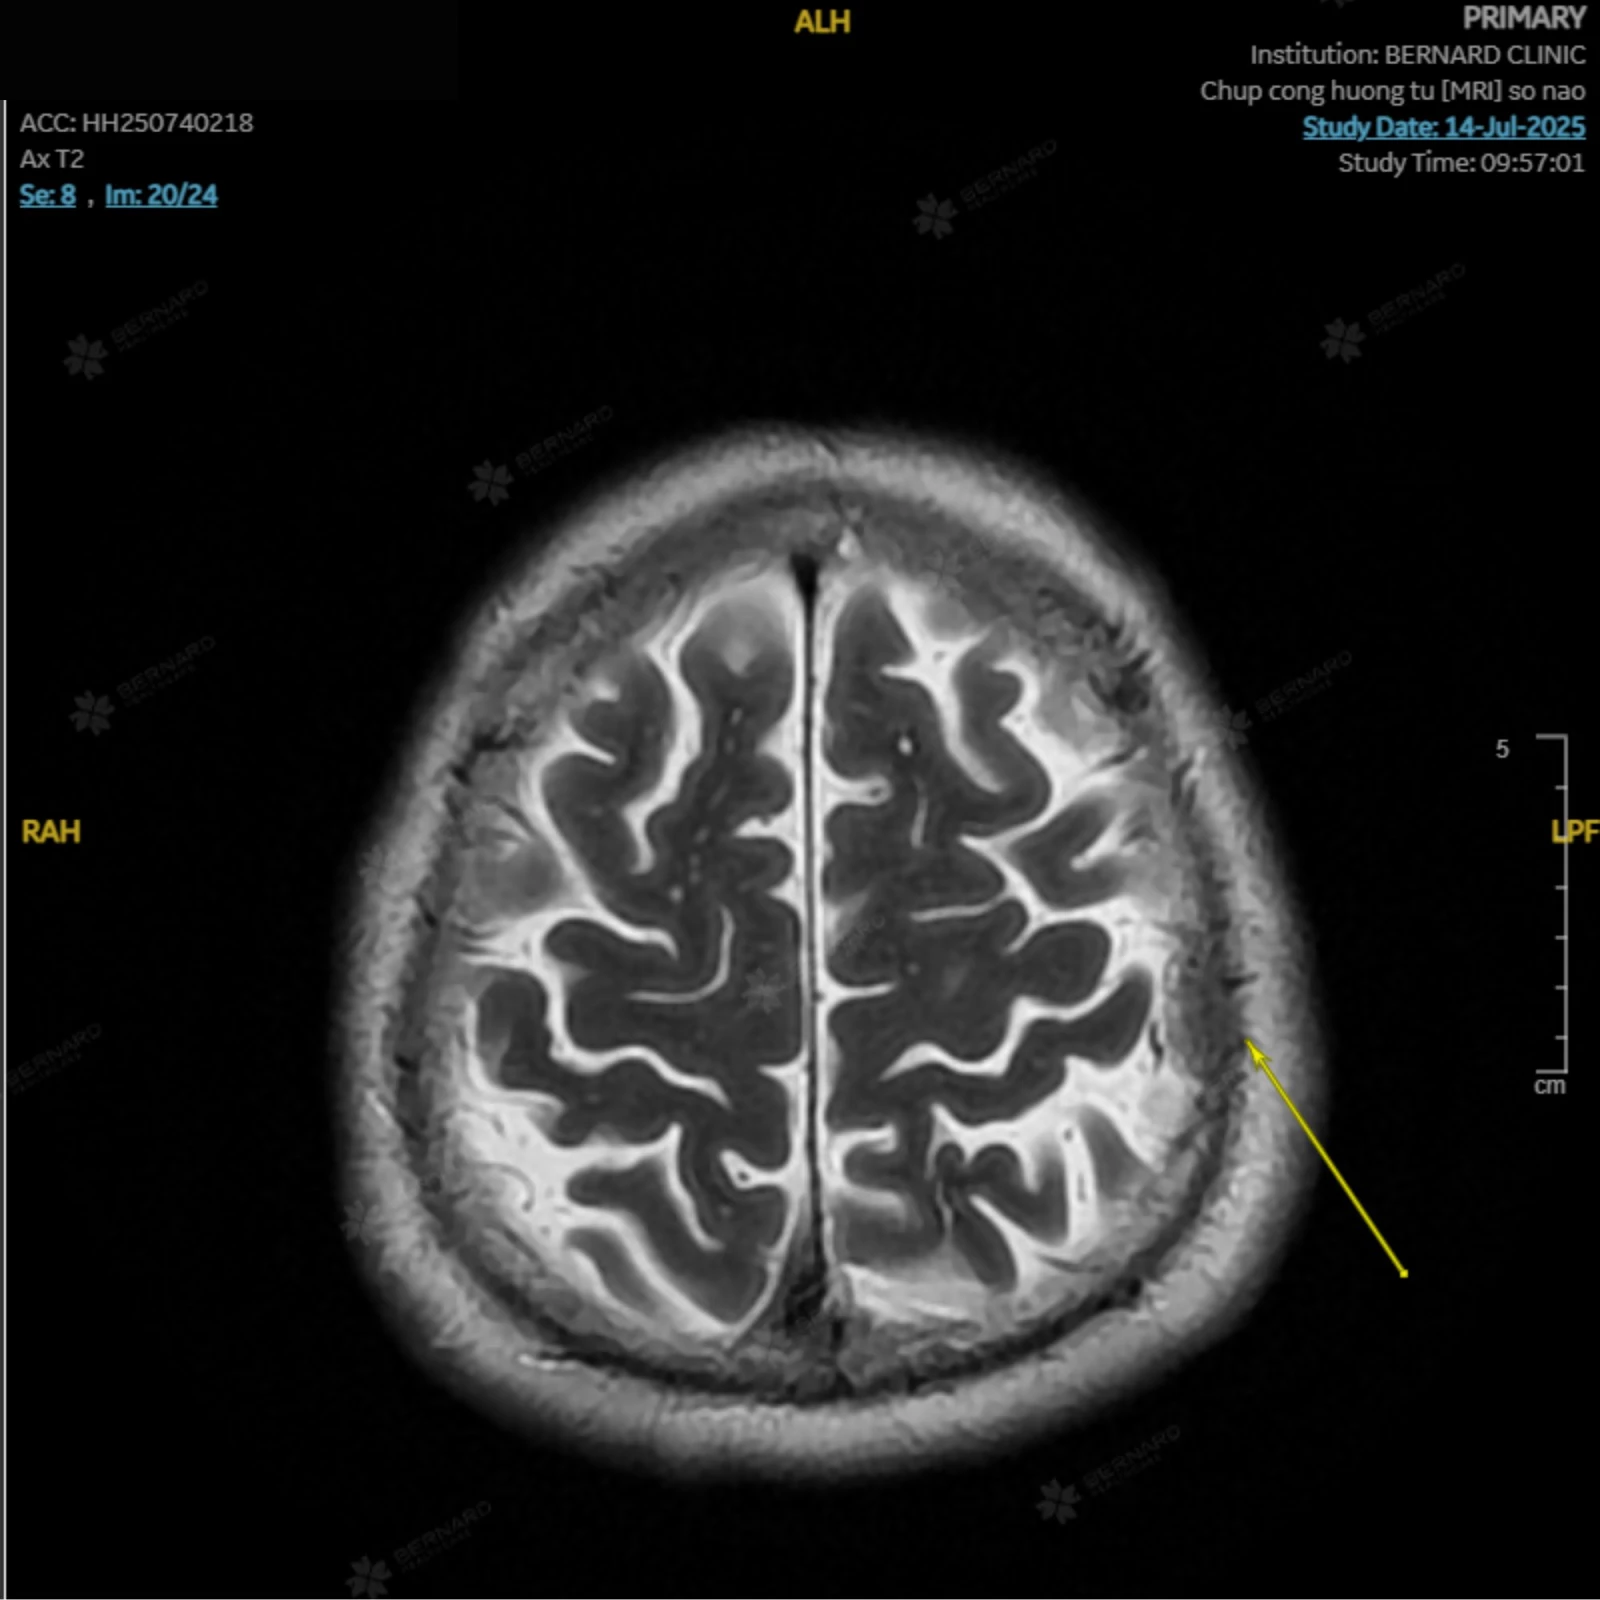

Kết quả phát hiện bất thường đáng lo ngại: Cấu trúc dạng choán chỗ ngoài trục đỉnh trái, kích thước #10x20x16mm (ngang x trước sau x cao), gợi ý u màng não nhỏ.

Theo đánh giá của bác sĩ Bernard, khối u hiện diện ở nam bệnh nhân có kích thước nhỏ, nhiều khả năng là lành tính, chưa gây ra triệu chứng ảnh hưởng đến sức khỏe nên chưa cần can thiệp ngay, có thể trì hoãn phẫu thuật. Dù vậy, bệnh nhân vẫn cần được theo dõi sát sao, tái khám định kỳ và chú ý theo dõi các triệu chứng bất thường để kịp thời xử trí, phòng ngừa các biến chứng.